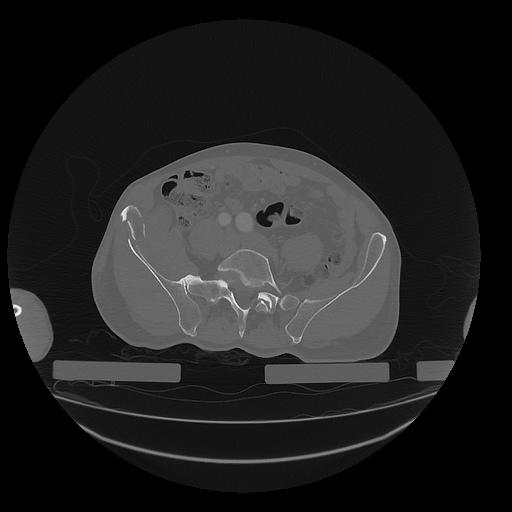

31 PULMON,CE,Vol,1.0,PULMON,,